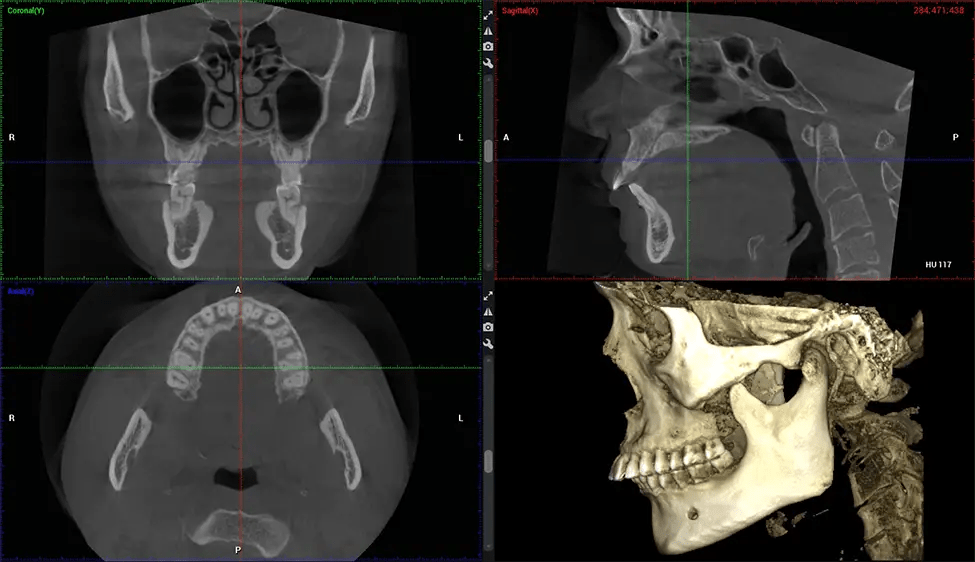

This 3D scan, called cone beam computed tomography, gives your dentist a more complete image of your oral anatomy and disease processes than a traditional X-ray. Unlike conventional X-rays, which capture a 2D image of your mouth from various angles, a 3D scan takes multiple digital X-rays for one image. It provides a complete view of your jaw, teeth, nerves, and soft tissues. This enhanced view allows dentists to detect minor issues not visible in traditional 2D scans, such as impacted wisdom teeth or bone fractures in the sinus cavity.

There are many benefits to using CBCT technology, especially compared to the traditional 2D X-ray format. One of the most significant advantages of CBCT scans is that they provide much more information than traditional X-rays. A scan lets your dentist see images from all angles of your jaw and mouth, including your sinuses, nasal cavity, cheekbones, and other surrounding areas. This added information helps your dentist craft a comprehensive treatment plan that addresses all aspects of your oral health.

Another significant benefit is that 3D imaging provides more precise images of your bone structure. These images are more detailed, providing you with a more accurate diagnosis. An accurate diagnosis means better treatment for you.

The patient is first positioned in the CBCT scanner, which typically consists of a rotating arm that houses the X-ray source and a detector. The patient’s head is immobilized to ensure accurate image capture. The X-ray source and detector rotate around the patient’s head, capturing various X-ray images from multiple angles. As the X-ray source rotates, it emits the cone-shaped X-ray beam towards the detector. The detector captures the X-ray images, which are then processed by the CBCT software.

After the scanning process, the captured X-ray images are processed by the CBCT software, which applies algorithms to reconstruct a detailed 3D image of the scanned area. The software compiles these individual X-ray images and creates a digital 3D representation of the patient’s anatomy. The reconstructed 3D CBCT image can be viewed and analyzed by the dentist or radiologist. This image can be manipulated, rotated, and zoomed in or out to examine specific structures and evaluate the patient’s condition.